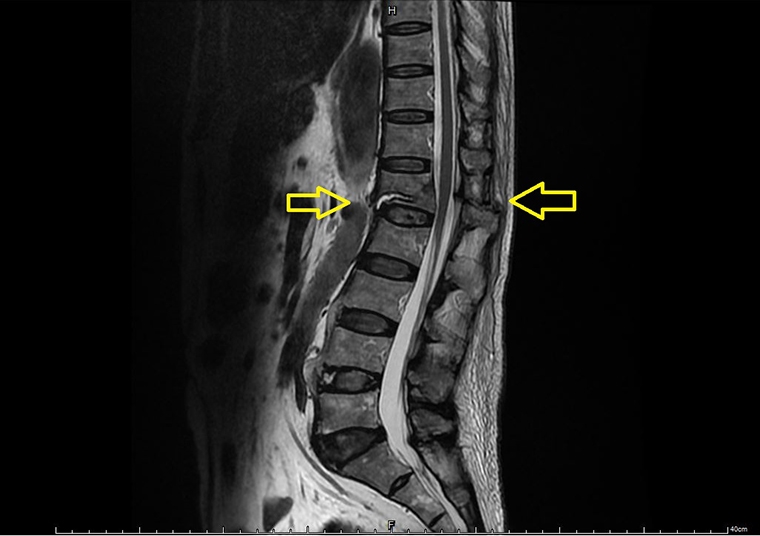

【NOW健康 陳如頤/台中報導】78歲的張先生日前在家中不慎跌倒後,背部持續疼痛。事發之初曾前往急診,被診斷為僵直性脊椎炎並僅給予消炎止痛藥,之後便返家休息。然而,1週後疼痛未見緩解,甚至需家人攙扶才能坐上輪椅。之後在家屬陪同下,轉往長安醫院骨科求診,經核磁共振檢查,最終確診為「屈曲牽張性骨折」(Chance fracture)。醫療團隊隨即為他安排微創脊椎固定手術,術後疼痛大幅改善,2週後回診時已能恢復日常生活,重拾行動自主。

長安醫院骨科喻大久醫師表示,僵直性脊椎炎是一種慢性發炎性疾病,會使脊椎逐漸融合,變得僵硬且失去彈性。在這樣的情況下受到外力撞擊或是跌倒時,比起一般老年人常見的脊椎壓迫性骨折,容易出現更為嚴重的屈曲牽張性骨折。

喻大久醫師進一步說明,脊椎的穩定結構分成前、中、後3個部分,而屈曲牽張性骨折是這3個結構全都受到破壞。前方椎體因彎曲力量而壓迫,後方的脊突及韌帶則因拉扯而斷裂,進而導致脊椎的不穩定。若不即時處理,可能會造成骨折移位而壓迫到神經,造成坐骨神經痛甚至出現下肢癱瘓。

幸運的是,張先生並未出現神經壓迫症狀,下肢肌肉力量與知覺皆正常。考量到脊椎不穩定的危險性,喻醫師迅速幫張先生安排從胸椎第十節到腰椎第四節的微創脊椎固定手術。